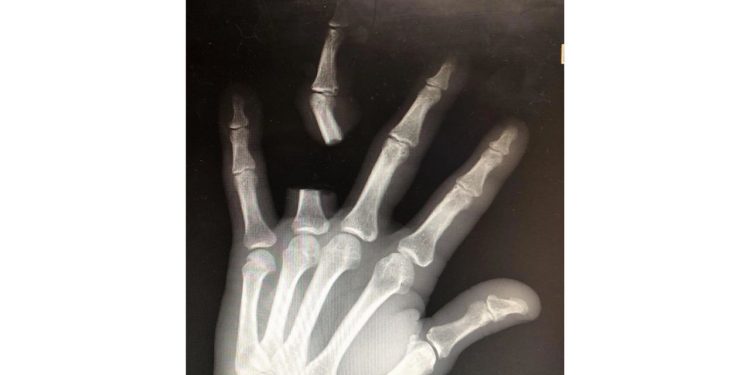

Após cortar o dedo, Zhang percorreu aproximadamente 80 quilômetros até um hospital, buscando atendimento emergencial. No entanto, ao chegar à unidade de saúde, foi informado pelos médicos que o réptil não possuía veneno letal. De acordo com os profissionais, o animal tratado como ameaça era, na verdade, uma espécie local não considerada perigosa.

Os médicos ainda relataram que não puderam reimplantar o dedo porque o idoso deixou o membro no local da ocorrência. Zhang passa bem, mas o caso ganhou repercussão na mídia chinesa e nas redes sociais como um alerta sobre decisões impulsivas em situações de emergência envolvendo animais peçonhentos.